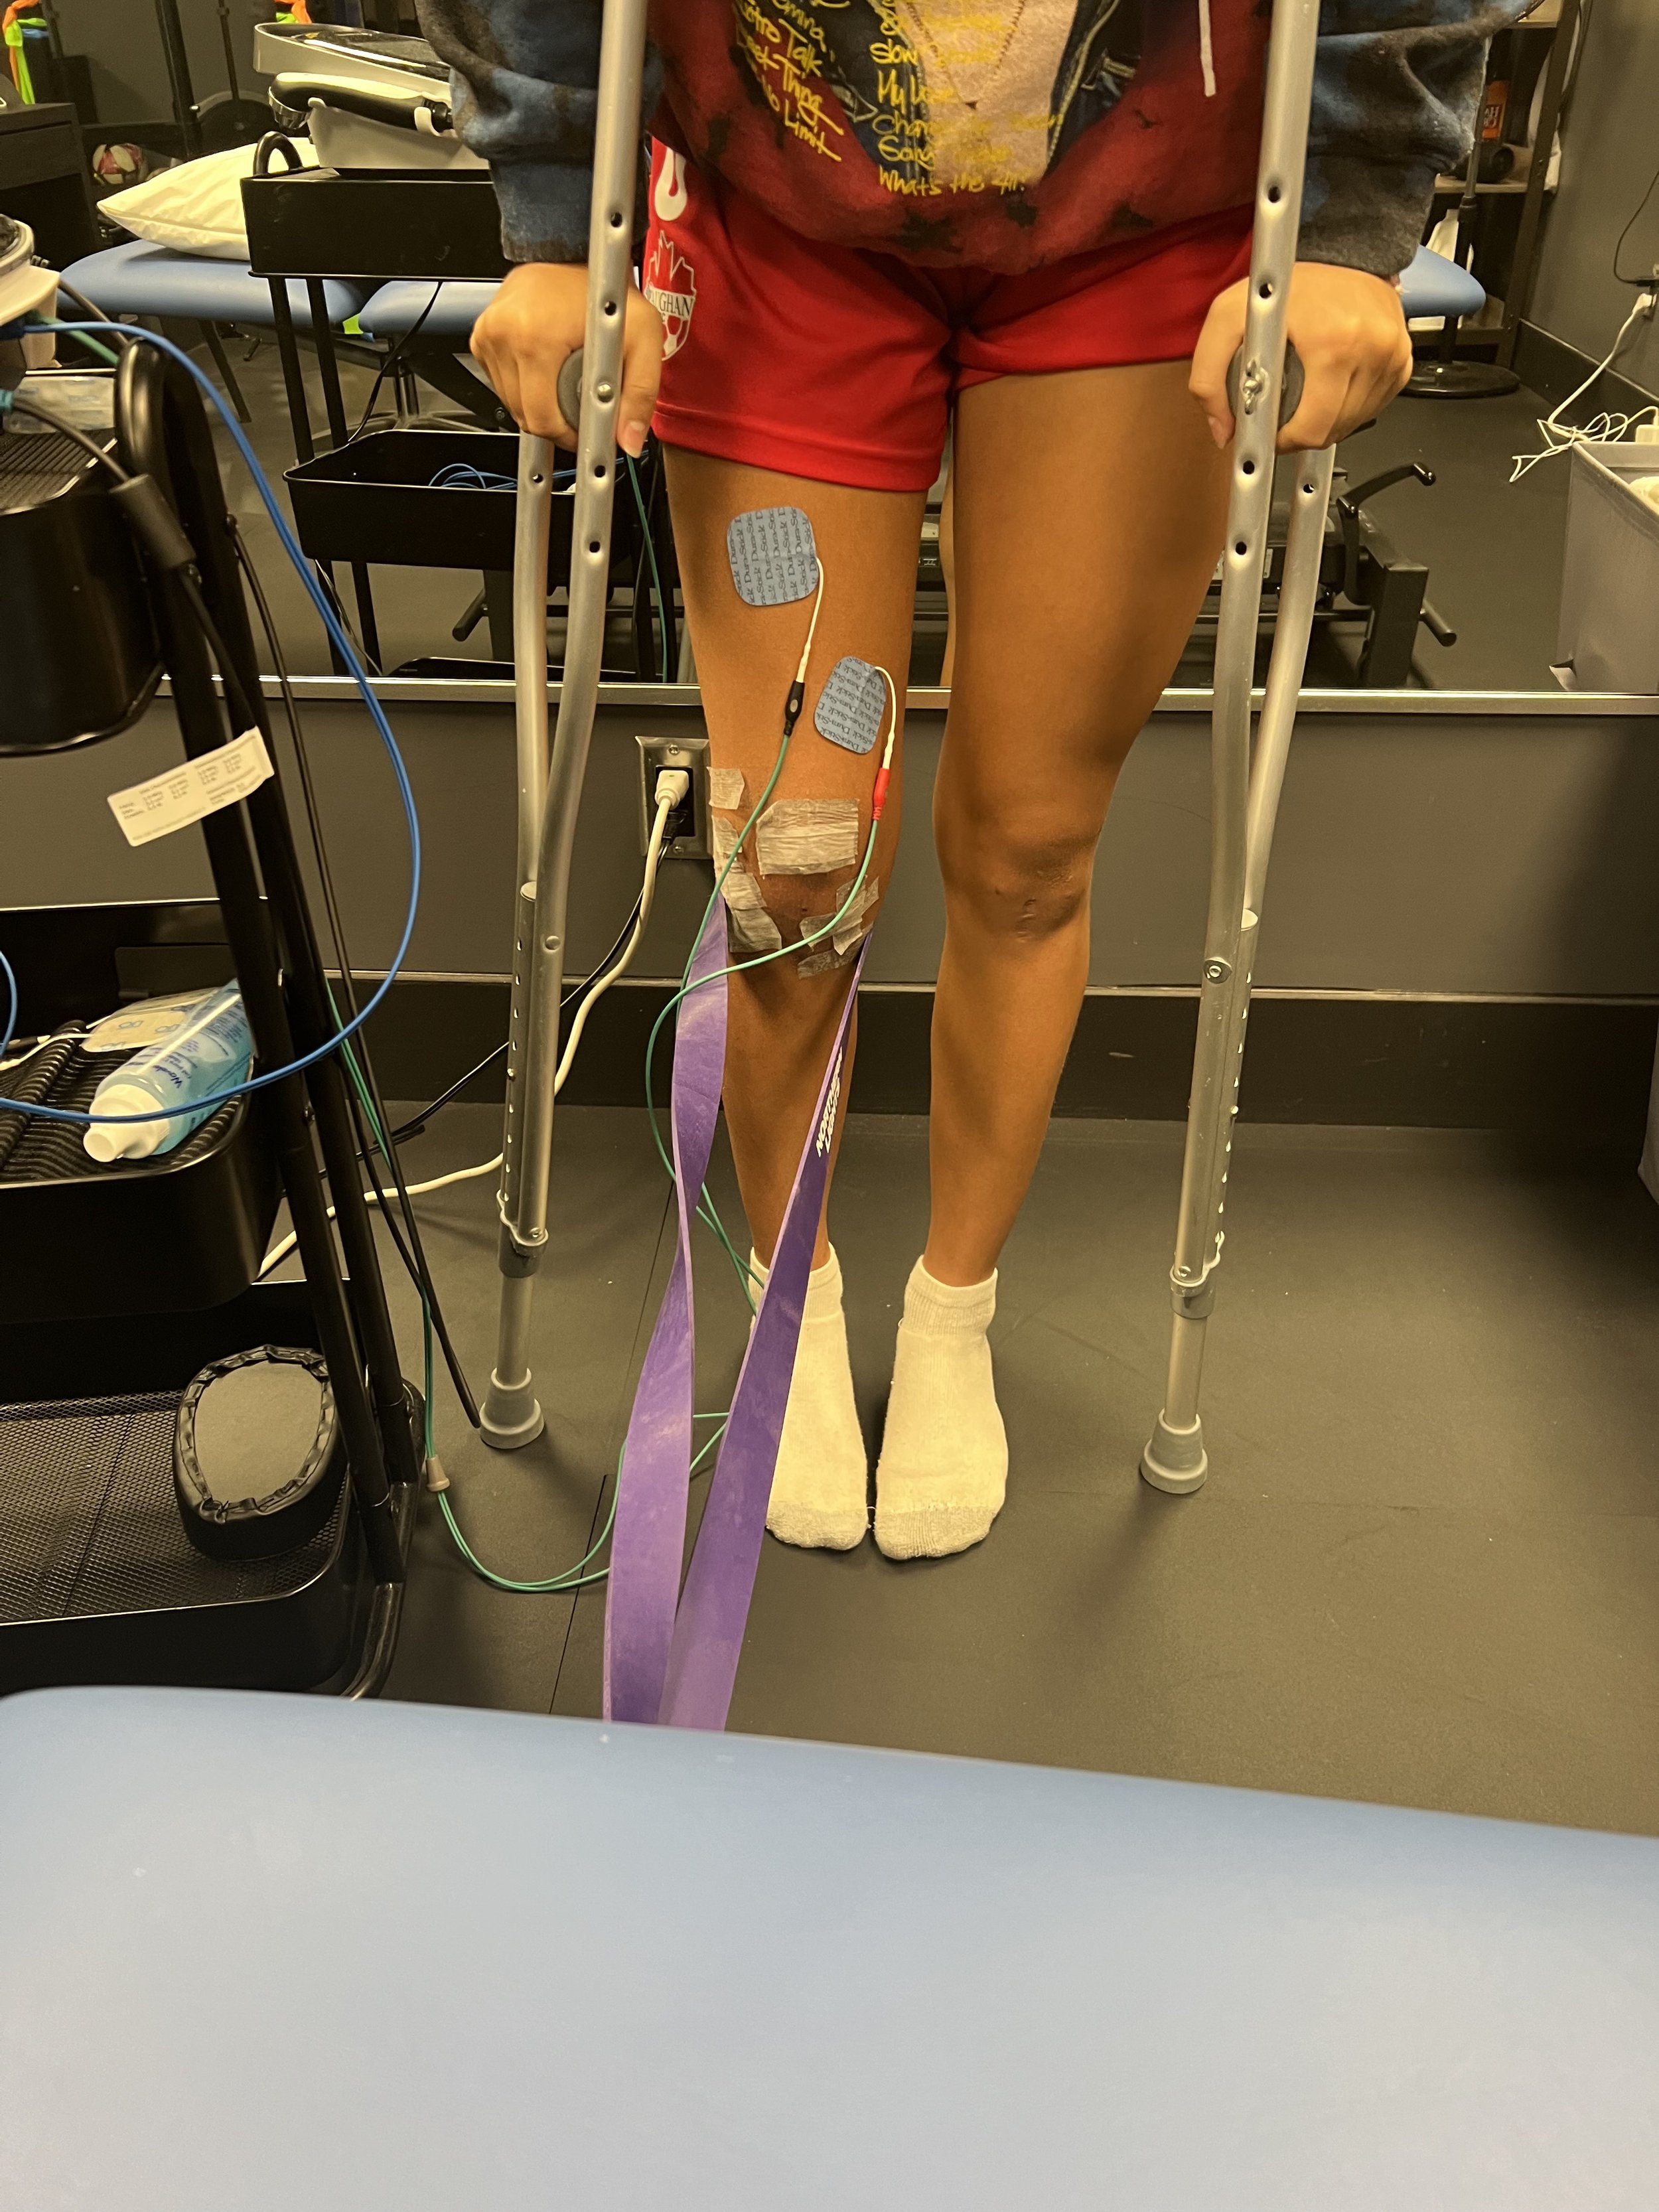

Knee Pain

ACL Assessment / Risk Management / Post Surgical Rehabilitation